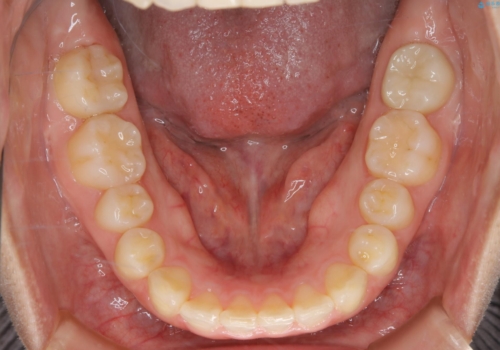

前歯のねじれと深い噛み合わせの改善:インビザライン治療

- 前歯が捻転していることを主訴に来院された方です。元々は部分矯正をご希望されていましたが、噛み合わせ等総合的に治療していくためインビザラインにて全顎的に治療を行うこととしました。

元々は上の前歯部の捻転のみの治療をご希望されていましたが、下の前歯もがたつきがあることや噛み合わせがかなり深いことを説明しました。後戻りのリスクを抑えるために全顎的な治療をご提案しました。

捻転していた上顎前歯部の仕上がりにこだわり、何度か修正を行ったため、満足のいく仕上がりになったと大変喜んでいただけました。